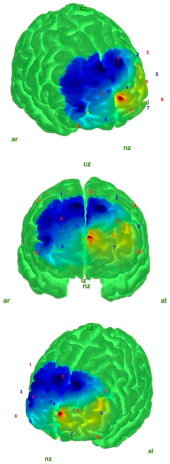

| Control | AIS | |

|---|---|---|

| EO |  |  |

| EC |  |  |